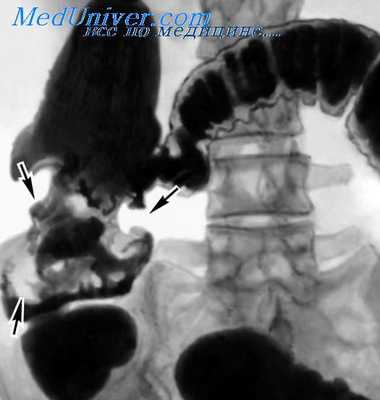

Наиболее частой локализацией рака прямой кишки является ампулярный отдел, реже — надампулярный и еще реже — анальная область. Среди 275 наблюдавшихся нами больных, страдавших раком прямой кишки, локализация в ампулярном отделе отмечена у 235 (85,4%), у 17 (6,2%) был надампулярный и у 23 (8,4%) — анальный рак. Эндофитная форма рака была у 101, экзофитная — у 174 больных.

Экзофитные опухоли имеют грибовидную форму или напоминают цветную капусту, растущую в просвет кишки, располагаются в зависимости от величины опухоли на небольшом участке кишечной стенки или могут занимать более полуокружности ее, иногда закрывают весь просвет. Эндофитные опухоли имеют вид ограниченных или более обширных язв с неровным инфильтрированным дном и с плотными валикообразными, не всегда сплошными краями. По сравнению с опухолями экзофитного типа край здесь более мягкий, а язвенный кратер глубже проникает в кишечную стенку.

Диффузный рак инфильтрирует кишечную стенку, лишает ее эластичности и превращает в узкий муфтообразный цилиндр на значительном протяжении по длиннику. Слизистая оболочка теряет обычную складчатость. Опухолевый процесс распространяется за пределы кишечной стенки в окружающую параректальную клетчатку.

Размеры опухолей прямой кишки на разных стадиях развития различные. Вначале они имеют вид небольших узелков. Затем могут быть в виде больших грибовидных разрастаний, занимающих значительную часть кишечной стенки, выполняющих просвет кишки. Язвенные формы имеют меньшие размеры — до 5—10 см в диаметре. Диффузные инфильтрирующие опухоли распространяются по всей окружности кишки, иногда занимают половину просвета и достигают 2/3 ее длины.

Рак верхнеампулярного отдела растет циркулярно, больше кпереди, проникает в серозную оболочку. Он долго остается в пределах стенок кишки, в результате чего кишка сохраняет подвижность. Опухоль является доступной для радикального вмешательства. С течением времени новообразование прорастает брыжейку сигмовидной кишки, распространяется на брюшинный покров, достигает стенок таза и позвоночника. Опухоли этой локализации нередко вызывают непроходимость кишечника.

Опухоли ампулярного отдела имеют вид ограниченных или обширных язв с неровным дном, инфильтрированными стенками и неравномерно возвышающимися краями. Они занимают одну из стенок кишки, иногда распространяются циркулярно и по длине. По выходе за пределы собственной фасции прорастают окружающую клетчатку и метастазируют.